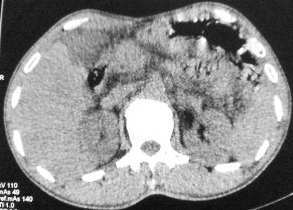

以下是引用butterylf在2005-12-21 19:10:00的发言:[br]我扫出来的图像都是这样的,窗宽窗位我参考了别的医院的啊,可是为什么我扫出来的图像质量不好,不好意思,是从显示器上拍的,而且还是用手机拍的,我不知道其他还能有什么方法拍啊!![br]病人是男性,41岁,[br]另外mas怎么调,不是不同的部位都要重新调过吧,?[br][br][br]对了,各位老师,我想问一个问题,我现在扫描片子打不出来了,这是为什么?ct已经传送过去了,可是激光打印就是出不来啊,打印机上总是显示close lower cover?这是为什么啊?